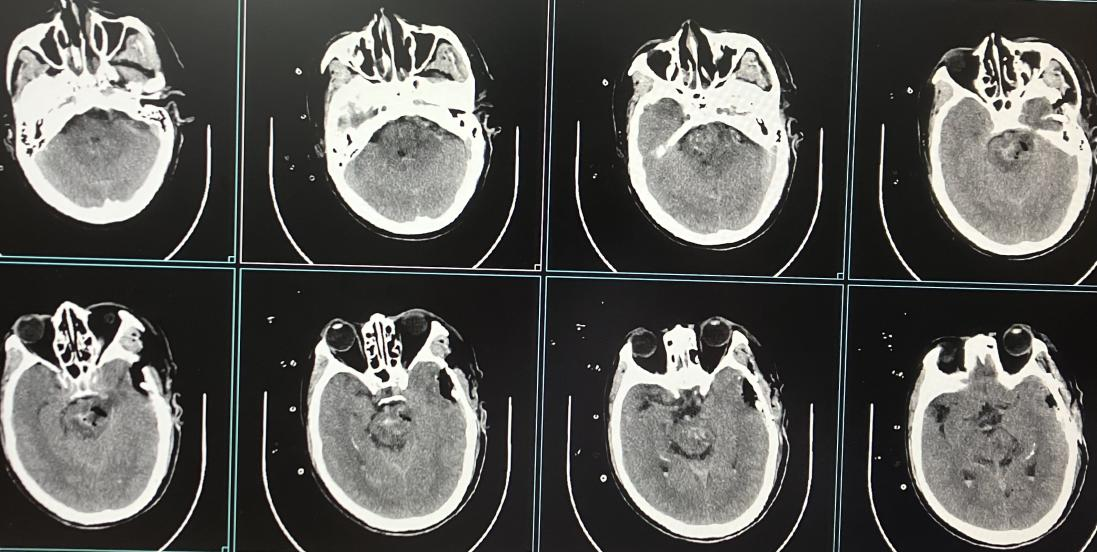

颅内巨大动脉瘤栓塞术(血流导向装置置入)

术前 术后

颅内动静脉畸形栓塞术

独立开展颅内动脉瘤、动静脉畸形、动静脉瘘、外伤性颈内动脉海绵窦瘘等介入栓塞治疗,已完成700余例,疗效显著。